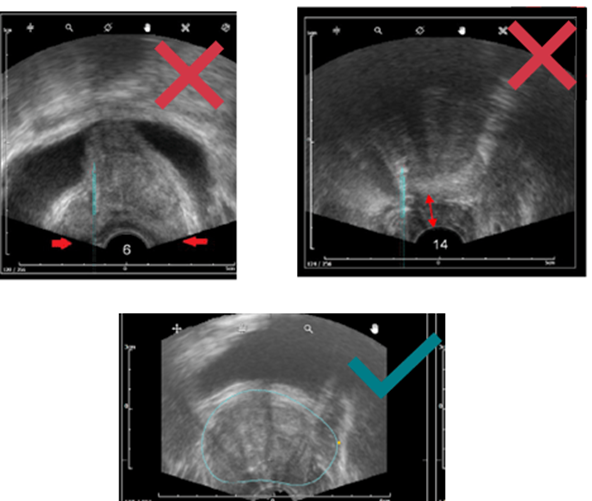

d. Pression sur la sonde et image

- Les lobes dépassent l’image (image de gauche (6)) → déformation de la glande due à une pression excessive sur la prostate).

- La prostate est trop loin de la tête de sonde (image de droite (14)) → pas assez de pression).

e. la zone de contour n’est pas bien ajustée

Tester la grille permet de vérifier l'ajustement de la zone de contour : elle doit s'adapter correctement au contour de la prostate.